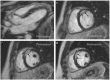

Sarcoidosis is a multisystem granulomatosis of unknown origin, which can involve almost any organ. Most frequently the disease involves the lungs and mediastinal lymph nodes, but it can affect the skin, the eyes, nervous system, the heart, kidneys, joints, muscles, calcium metabolism, and probably any other anecdotical organ involvement. Cardiac sarcoidosis is one of the most challenging involvements, as it can lead to cardiac mortality and morbidity, and also because the diagnosis may be difficult. With no specific symptoms, cardiac sarcoidosis may be difficult to suspect in a patient with no previous extra-cardiac sarcoidosis diagnosis. This manuscript reviews the current knowledge of the diagnosis and decision to treat cardiac sarcoidosis, and illustrates the information with a case presentation of a young adult with no risk factors, no previous diagnosis of sarcoidosis, and with cardiac symptoms impairing his quality of life.